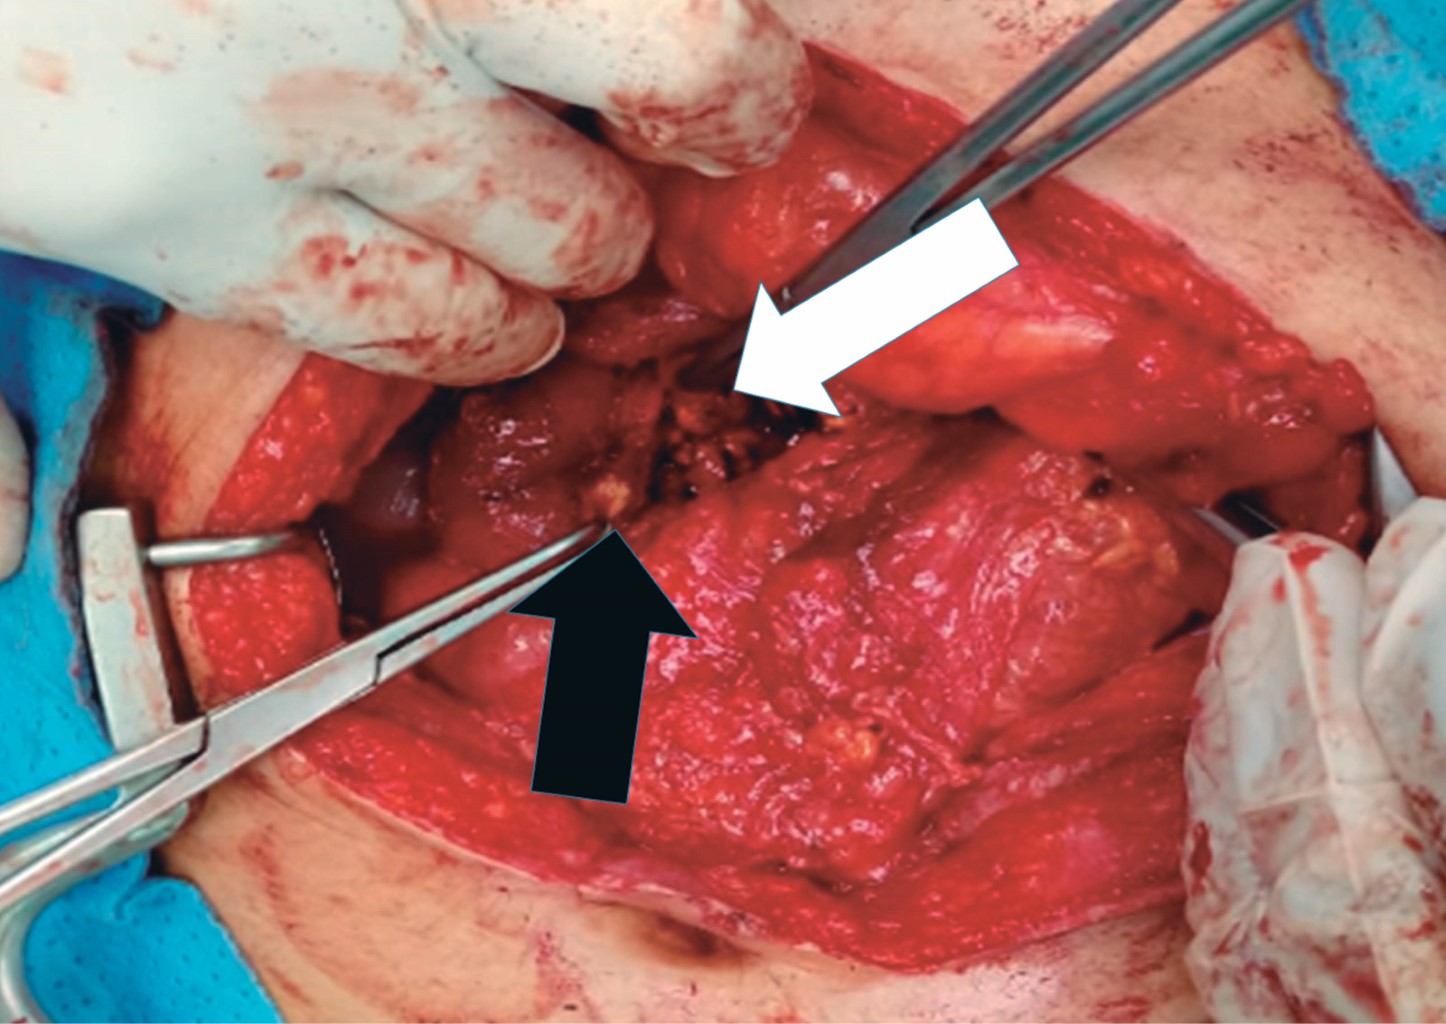

La paciente fue sometida a laparotomía exploradora donde se identifica masa tumoral de aproximadamente 6 × 8 cm a nivel de la cabeza del páncreas adosada a la segunda porción del duodeno, por lo que se procede a realizar enucleación por medio de disección de segunda porción de duodeno y porción transpancreática involucrando conducto pancreático principal, se realiza tutorización del mismo con sonda Nélaton No 12, exteriorizándola a través de segunda porción del duodeno hacia la pared abdominal a la altura del flanco derecho, siendo fijada con sutura de polidioxanona PDX 3.0 (Figuras 2, 3 y 4).

Figura 2